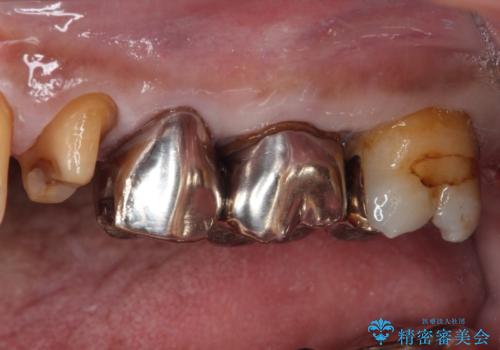

精査の結果、詰め物の下に虫歯が大きく広がっているのがわかりました。

虫歯の範囲が大きく、部分的な詰め物では対応が難しいため、オールセラミッククラウンにて補綴することとしました。

また虫歯除去の際に、万一根管と交通してしまっても根管に感染を起こさないために、ラバーダム防湿をして虫歯除去しました。